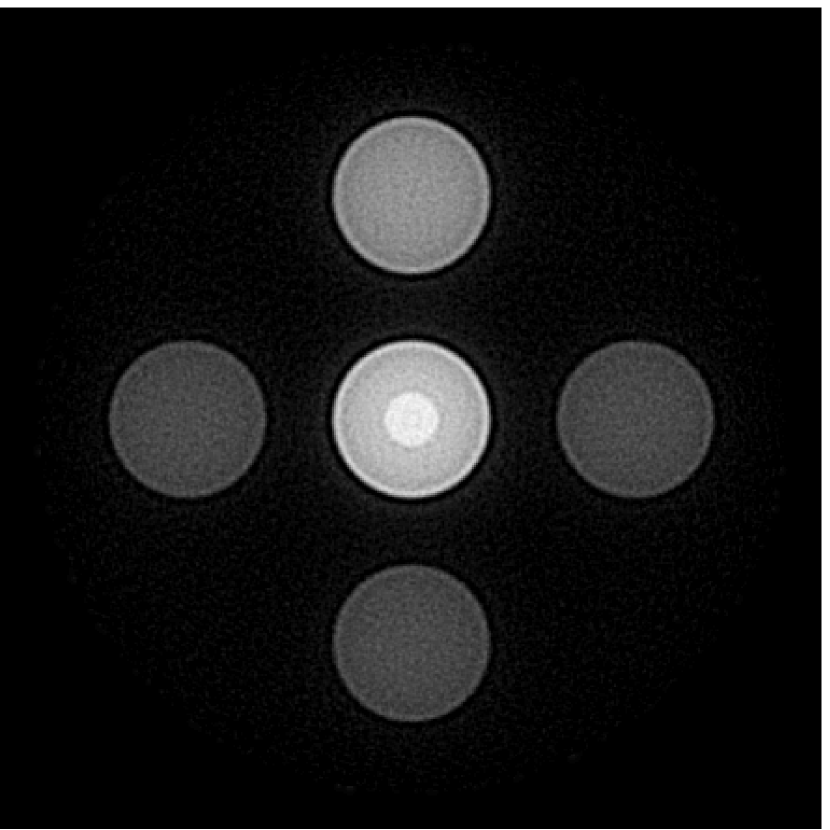

Figure 2(a) shows the image reconstructed by use of the conventional iterative method that utilized a system matrix based on EIR-2. Different values of the regularization parameter from the interval were considered. The reconstructed image with the value of that minimized the RMSE was chosen to represent the best performance of the conventional iterative method. Figure 2(a) and the profile in Figure 2(c) demonstrate that the use of an inaccurate EIR can result in strong artifacts and distortions in images reconstructed by use of the conventional methods.

When the VP algorithm was applied, different values of the regularization parameter from the interval and from the interval were considered. The image that minimized the RMSE was chosen and displayed in Figure 2(b). As revealed by this image and the profiles in 2(c), the VP algorithm yielded an image with fewer artifacts and distortions, and image fidelity was improved as reflected by the reduced RMSE.

Figure 7(a) reveals that use of the inaccurate EIR in the conventional iterative method created strong artifacts and distortions. Figures 7(b) confirms that the artifacts and distortions were significantly mitigated when the VP method was employed. Image profiles for both cases are shown in Figures 7(c). The overall accuracy of the recovered EIR, shown in Figure 7(d) and 7(e), was improved, but it contained spurious oscillations.